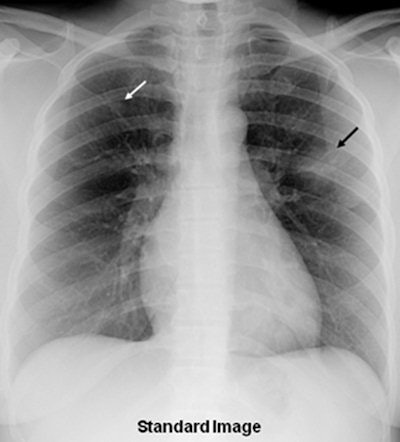

Thanks to its ability to improve the conspicuity of focal lung disease, bone suppression image processing can significantly improve radiologists' accuracy in identifying focal pneumonia on chest radiographs, according to new research published online on 5 July by European Radiology.

Bone-suppression techniques have been shown to improve diagnostic accuracy in detecting lung nodules, but the researchers sought in their current study to evaluate the software's impact on radiologists' performance for detecting focal pneumonia.

"Focal pneumonias were frequently difficult to detect on the standard [chest x-rays] but were relatively more conspicuous, and therefore easier to detect on the [bone-suppression imaging] images," the authors wrote.